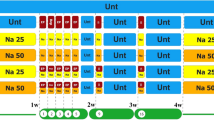

Before NLC could be used as a nanocarrier for AM delivery, the cytotoxicity of blank NLC was ascertained. The prepared NLC was composed of liquid and solid lipid, and surfactant(s). Therefore, we sought to determine the appropiate concentration of NLC for GC-1 spermatogonia cell line. The concentration of NLC was decreased by dilution of the NLC stock solution (100 mg/ml). Cell viability of GC-1 cells was examined after 24-h exposure to 0–1000 μg/mL NLC. As shown in Fig. 3a, the 250–1000 μg/mL NLC displayed less than 1% cell viability, increasing to 80% for 125 μg/mL, and no adverse effect (100% cell viability compared to the untreated cells) was observed for 62.5 μg/mL. Therefore, the optimal concentration for GC-1 cells was determined to be 62.5 μg/mL NLC. Based on this, further analysis was carried out by using this concentration. Similar results were observed in NLC-treated BJ Foreskin fibroblasts.

Cytotoxicity of blank NLC at various concentrations in GC-1 cells (mouse spermatogonium). (a) Following 24 h incubation with NLC, cell viability was determined by the CellTiter-Glo® cell viability assay. Mean cell viability was normalized to untreated controls, with the mean + SEM of n = 3, from one representative experiments of three independent experiments. Statistical analysis was performed using two way ANOVA, ***p < 0.001. (b) Morphological characteristics of mouse spermatogonium cell were visualized under the fluorescence microscope. Cells were stained with the reagents in the LIVE/DEAD® cell viability/cytotoxicity Assay Kit. Dead and live cells fluoresce red-orange and green, respectively. (Scale bar: 200 μm).

Spermatogonium cell death induced by AM-NLC

Next we investigated the effect of AM-NLC on proliferation of GC-1 spermatogonia cells and the mechanism. This was compared to blank NLC by using the predetermined concentration of NLC in order to show that the cytotoxicity of AM-NLC was due to the active compound, AM. Cells were treated with AM-NLC or blank NLC (62.5 μg/mL). This dilution was approximately equal to 6.25 μM of AM. Our results showed that the cell viability of AM-NLC-treated cells was drastically decreased as shown in Fig. 4a,b. In contrast, no cytotoxicity was observed in cells treated with blank NLC. Moreover, foreskin fibroblast cells were treated with the correspoding concentration of AM-NLC or blank NLC. No cytotoxicity was observed in foreskin fibroblast cells treated with blank NLC or AM-NLC, suggesting selective killing of spermatogonium cells induced by AM-NLC (Fig. 4a,b).

Male germ cell death induced by AM-NLC. (a) Cytotoxicity of AM-NLC or blank NLC in spermatogonia and foreskin fibroblast cell lines. Following 24 hr incubation with blank NLC or AM-NLC, cell viability was determined by the CellTiter-Glo® cell viability assay. Mean cell viability was normalised to non-treated controls. (b) Viability characteristics of mouse spermatogonium and foreskin fibroblast cells were visualized under the fluorescence microscope. Cells were stained with the reagents in the LIVE/DEAD® cell viability/cytotoxicity Assay Kit. (Scale bar: 200 μm). (c) Bright-field and fluorescence images display morphology and Annexin V/PI staining of spermatogenic cells after treatment with NLC or AM-NLC at diiferent time points and heat-induced necrotic cells for comparison. (Scale bar: 200 μm). (d) Determination of apoptosis. Caspases 3/7 activity were examined as indicators of apoptosis. Green and red fluorescence staining around cells indicates Annexin V-FITC and PI staining, respectively.

To gain a closer insight into AM-NLC-induced biological effects on GC-1 spermatogonia cells, Annexin V/PI staining and Caspases 3/7 activity were examined as indicators of apoptosis. To examine early and late apoptotic cells in AM-NLC-exposed cultures, fluorescence microscopy was performed using Annexin V-FITC and PI. As shown in Fig. 4c, control cultures treated with blank NLC remained unstained (Annexin V-FITC−/PI−). After 1.5 hour of exposure to AM-NLC, early apoptotic cells exhibited Annexin V-FITC+/PI− staining patterns; whereas late apoptotic cells showed Annexin V-FITC+/PI+ staining patterns after 6 hour post-treatment. In contrast, after 1.5 hr induction of heat-triggered necrosis, cells exhibited strong PI staining, which identifies primary necrotic cells19. In addition, the results showed that AM-NLC significantly increased the activities of Caspases 3 and 7 (Fig. 4d).

Cell death and survival in seminiferous tubules of cat testis after AM-NLC treatment

Treatment of intact seminiferous with AM-NLC was optimized to achieve high mortality by varying concentrations of NLC or AM-NLC (0–2,000 μg/mL). As shown in Fig. 5a, the result shows a significant cell death in seminiferous tubule’s testicle treated with 500 μg/mL AM-NLC. In addition, cell viability was decreased in a dose-dependent manner. The result also shows a difference in seminiferous tubules cross-section between the control blank NLC- and AM-NLC-treated groups. As shown in Fig. 5b, blank NLC-treated testicular explants showed mostly normal testicular anatomy with an orderly arrangement of germ cells and Sertoli cells and normal stages of spermatogenesis. In contrast, AM-NLC treatment induced the degeneration of germ cells within seminiferous tubules. Tubules were shrunken and greatly depleted of germ cells. (Fig. 5b).

Cell death in seminiferous tubules of cat testis after AM-NLC treatment. (a) After 48 h incubation with various concentrations of blank NLC or AM-NLC, cell viability in seminiferous tubules was assessed by the CellTiter-Glo® cell viability assay. Mean cell viability was normalized to untreated controls, with the mean of n = 3 + SEM, from one representative experiments of three independent experiments. Statistical analysis was performed using two-way ANOVA, ***p < 0.001. (b) Photomicrograph of the seminiferous tubules. Testes tissue explants were obtained from the castrated testes. Images represent hematoxylin and eosin-stained sections of teticular explants after 48 h treatment with blank NLC or AM-NLC.